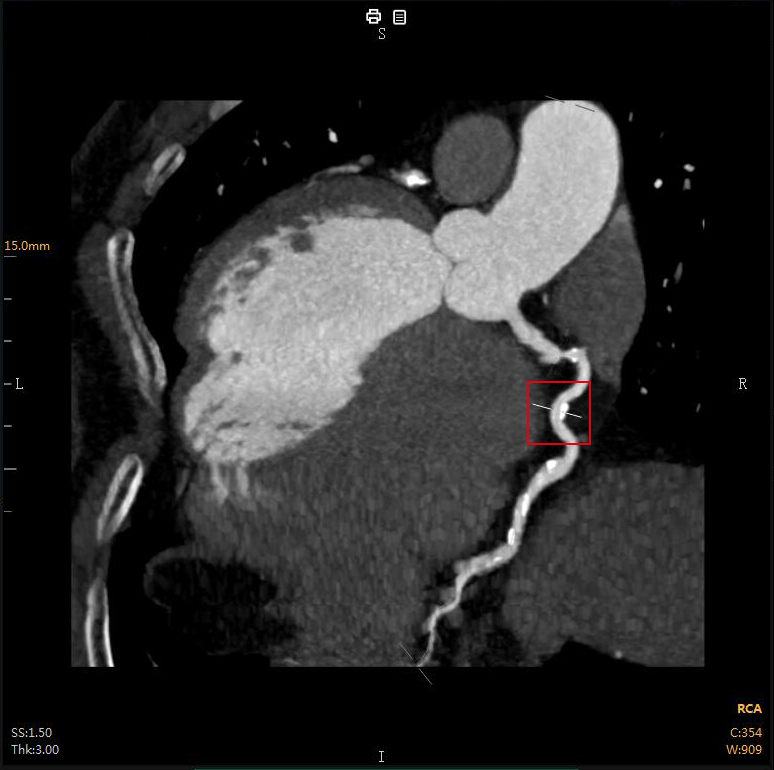

“CTA冠脈全自動(dòng)診斷”

Automatic Coronary Diagnosis

全自動(dòng)圖像重建/分割

全自動(dòng)量化測量

云端AI的CTA冠狀動(dòng)脈全自動(dòng)診斷

重構了CTA冠脈檢查的極簡(jiǎn)流程